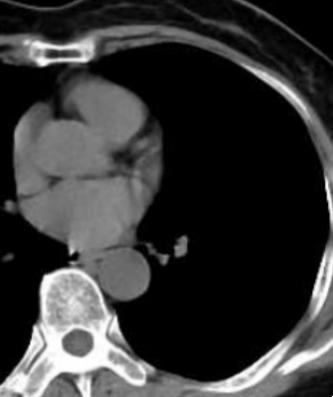

7月22日林女士遵照刘先领教授医嘱复查肺部CT,神奇的一幕出现了,其原左下肺“恶性肿瘤”完全消失,林女士免除了一次全麻大手术带来的风险,节省了高达数万元的医疗费用,更重要的是保住了计划切除的重要脏器(肺叶),全家人喜极而泣。

2023年7月20日(抗炎治疗后结节消失)